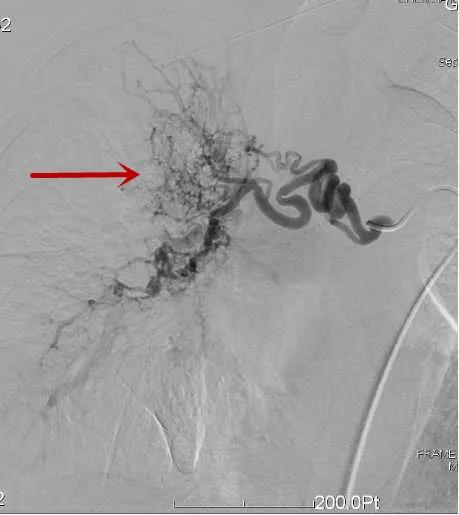

大咯血介入治疗

△术中见肝内血管片破裂出血/栓塞后肝出血动脉已闭塞